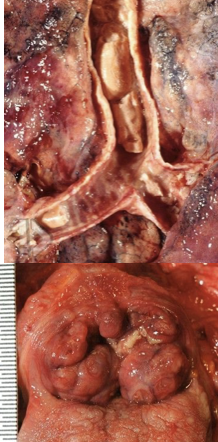

epidural hematoma

laceration of the middle meningeal artery

breaking of temporal bone

bleeding between dura and skull

subarachnoid hematoma

rupture of AVM or aneurysm, head injury

bleeding within the subarachnoid space

subdural hematoma

typically from trauma

tearing of the bridging veins, between brain and dura